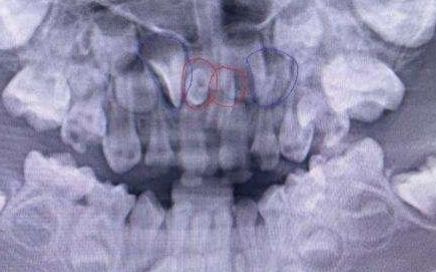

一般成年人的牙齿在二十八到三十二的范围之内都属于正常现象,如果不再这个范围之内的话就是异常现象了。这些不正常的情况常常是由于牙胚发育异常造成的,多余三十二颗牙齿的称为“多生牙”,少于二十八颗牙齿的称为“缺额牙”。

多生牙一般发生在中切牙区,还有的埋伏在颌骨内。缺额牙大多常见于上颌侧切牙以及下颌第二前磨牙,一般都是对称性发生的,通俗的来讲就是如果你左边没有长出,大概率的右边也不会有……